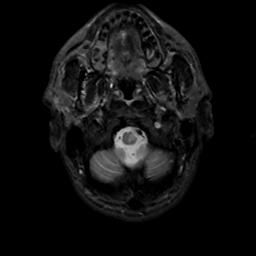

MR Study #6, March 17, 1991 -- Slice #3

[Home][Help][Clinical][Tour 1][Tour 2] Slice 3